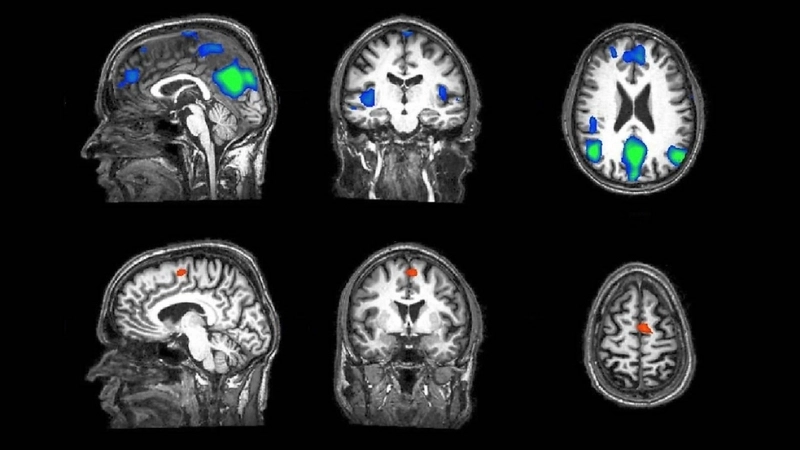

• Giải phóng hóa chất nội sinh: Khi bạn tin rằng mình đang dùng một loại thuốc giảm đau hiệu quả, não bộ có thể được kích thích để tự sản xuất ra các chất giảm đau tự nhiên như endorphin. Các nghiên cứu hình ảnh não bộ (fMRI) cho thấy các vùng não liên quan đến cảm giác đau thực sự giảm hoạt động sau khi dùng giả dược.

Khám phá cơ chế hoạt động của placebo qua hình ảnh fMRI não bộ